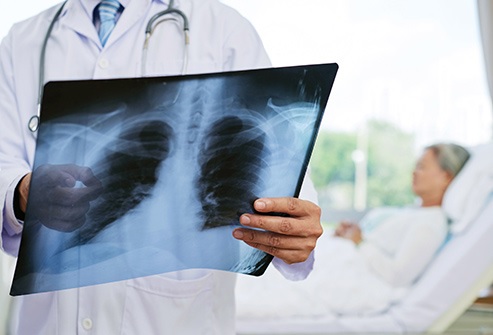

Pneumonia

People over 50 are at higher risk of the kind of pneumonia caused by bacteria, not the one caused by a virus. Called pneumococcal pneumonia, it can be life-threatening. Older people are more likely to get it because your body’s immune system gets weaker as you age. But there’s a vaccine for it, and the CDC recommends it for everyone over 65.